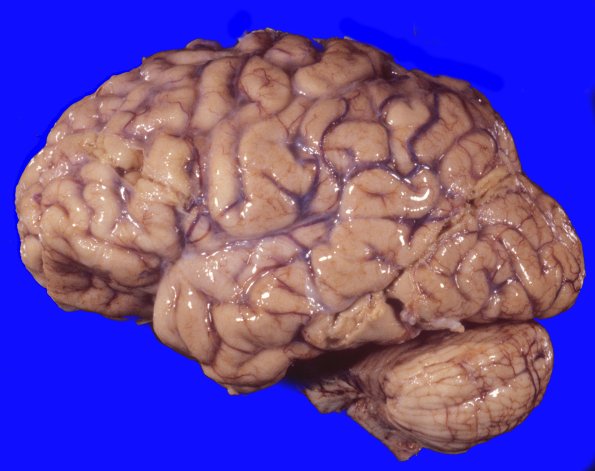

Huntington Disease

The hemispheres show diffuse, mild atrophy manifested by narrowed gyri and widened sulci.